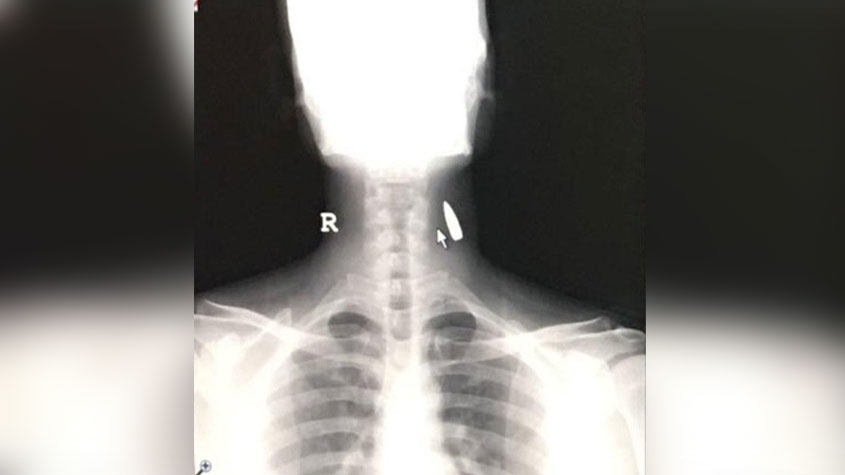

نجاة وافد هندي بـ #الطائف اخترقت رصاصة مجهولة رقبته